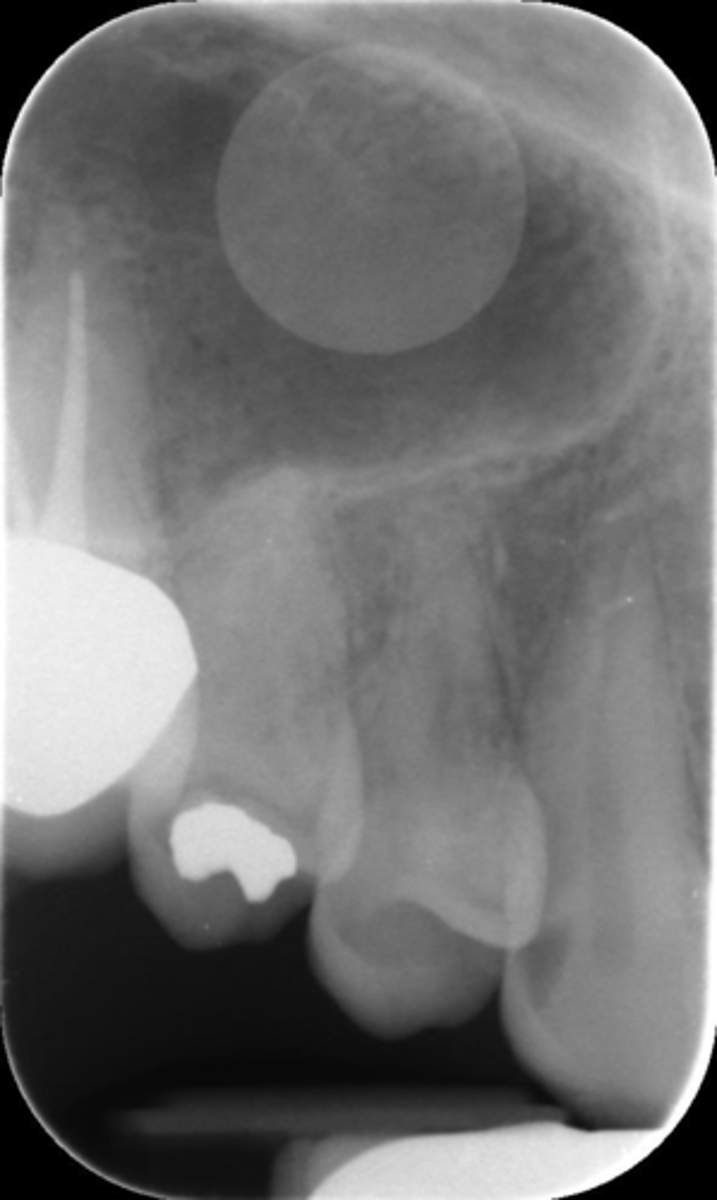

What is this error?

Horizontal angulation, no apices show, vertical angulation

Cone cut, rotation